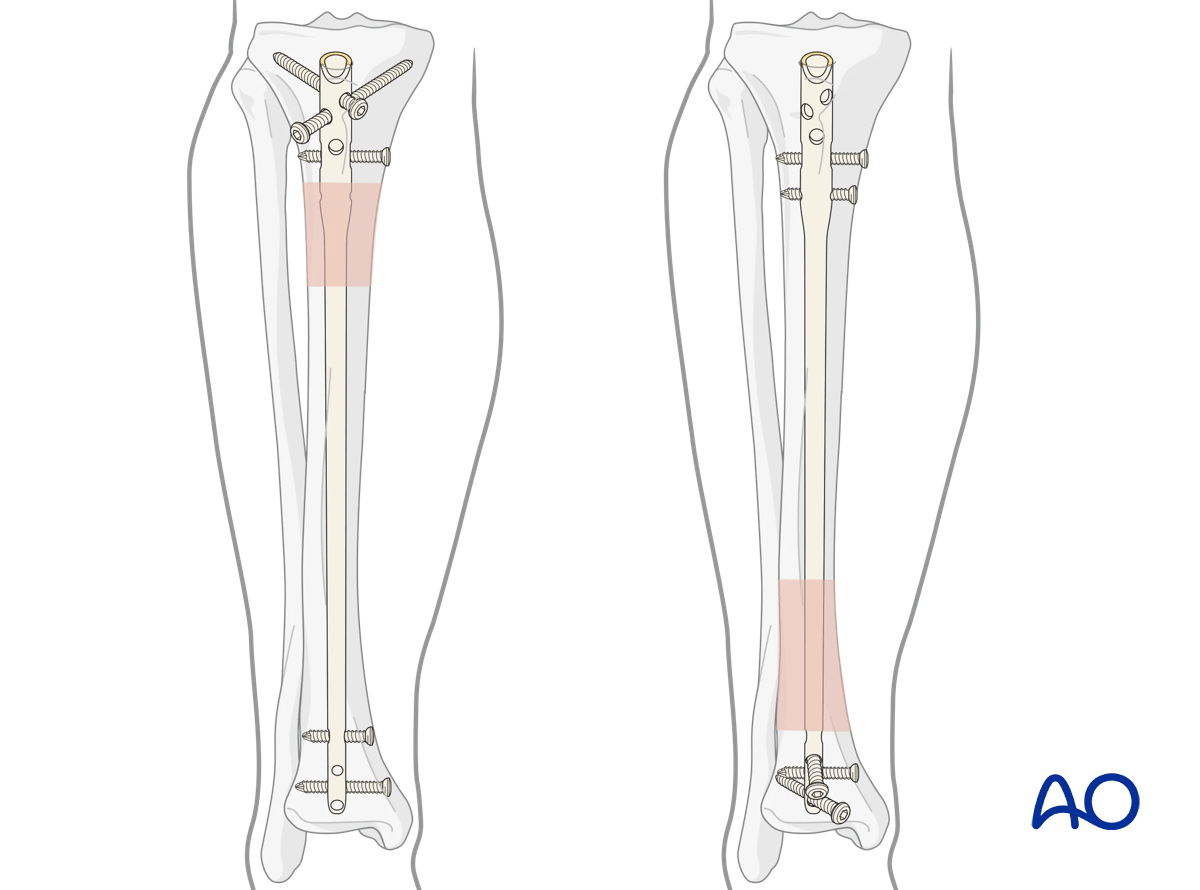

Intramedullary fixation is suitable for the majority of diaphyseal and metadiaphyseal tibial fractures. With newer nail designs and attention to technique, nailing can be extended to both proximal and distal extraarticular fractures. Suprapatellar nailing is ideal in managing fractures at these anatomic sites. In the semi-extended position the knee is flexed approximately 15–20° making it is easier to reduce the fracture and maintain reduction with this surgical technique.

Modern IM nails permit placement of locking screws through bone and nail, to improve fixation both proximally and distally. Locked nails permit stable fixation which controls length, rotation, and alignment. Some nails offer fixed angle locking of screws proximally and distally. Fractures involving the proximal and distal segments of the tibia should have a minimum of three screws placed in the short segment to enhance fixation.

With proximal fractures, multiple locking screws may be required for adequate stability. Their choice usually depends upon the fracture pattern. For diaphyseal fractures, a single locking screw may be sufficient, if the fracture is length-stable. (Use of an oval (“dynamic”) hole will permit fracture impaction while controlling rotation.) If the fracture is length-unstable, two or three proximal locking screws should be used, for better maintenance of length. Fractures involving the proximal and distal segments of the tibia should have a minimum of three screws placed in the short segment to enhance fixation.

Screw insertion

Typically, two distal locking screws are used for diaphyseal or proximal fractures, though if the pattern is length-stable, a single screw may be sufficient. A minimum of three proximal locking screws should be used for proximal fracture patterns. Distal fractures should have multiple distal screws (a minimum of three) including AP and/or oblique orientation to provide adequate stability. Repeat the above technique as necessary for each screw.